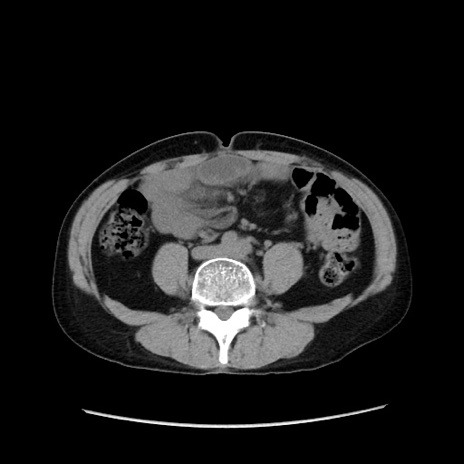

症例37(横断像)

【症例】40歳代 男性

【主訴】腹痛

【現病歴】4時間ほど前に電車に乗車中に臍部上より腹痛出現。徐々に増悪し起立困難となり、救急外来受診。生ものは数日食べていない。今朝お雑煮を食べた。

【身体所見】BT 36.8℃、BP 117/84mmHg、HR 91/min、SpO2 97%、苦悶様、腹部:臍上部広範囲圧痛あり、反跳痛±

【データ】WBC 8100、CRP 0.03